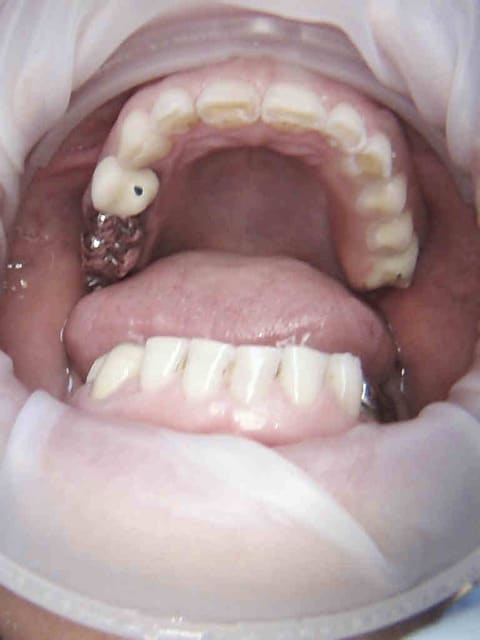

Cas concret comment tu traites ce cas yobi sachant que le mutuelle de la patiente rembourse 200 % sur les IC, 300 % les couronnes en postérieur, et 400 % les couronnes en antérieur ?

Cheese ! On a bien négocié hein ? -)))))) magnifique ! toutes les dents sont fusillées, plus de sensibilité au froid, ca coute une blinde (remboursée ++++) mais quel confort !